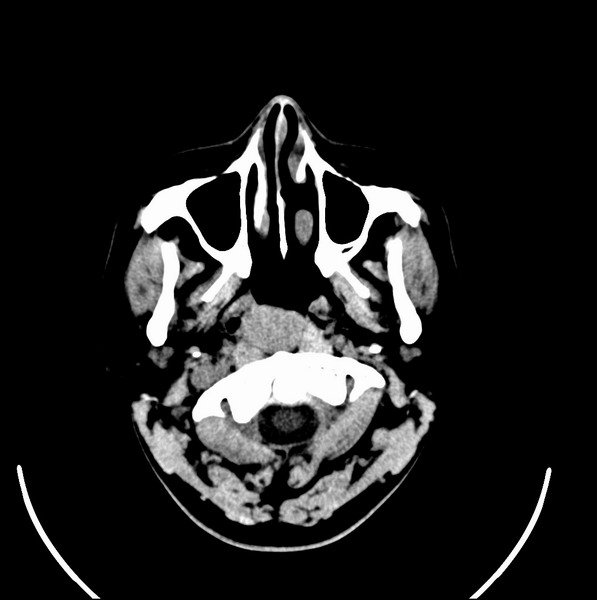

扫描示鼻咽腔不对称,中度狭窄,右侧咽隐窝消失,局部软组织肿块,鼻咽右侧壁增厚形成肿块,突入鼻咽腔,肿块平扫呈等密度,肿块向深部侵润,右侧翼内外肌受侵,右侧咽旁间隙变窄;向后生长,头长肌界线欠清,向后上生长侵犯同侧颈动脉鞘区。双侧海绵窦增宽,内见软组织影与鼻咽部肿块相连。考虑鼻咽癌。鼻咽癌主要是放射治疗,且效果较好;到当地有治疗设备较大医院治疗即可。

这个病例有点特殊,和常见的鼻咽癌不太一样,以向颅内侵犯为主,骨质破坏区小。鼻咽癌首先要考虑,有没有其他可能?本人不会看mr片,期待有人能讲解,期待病理。

鼻咽部新生物(纤维血管瘤?鼻咽癌?)侵犯右侧中颅窝底及右侧海绵窦;建议必要时活检定性。